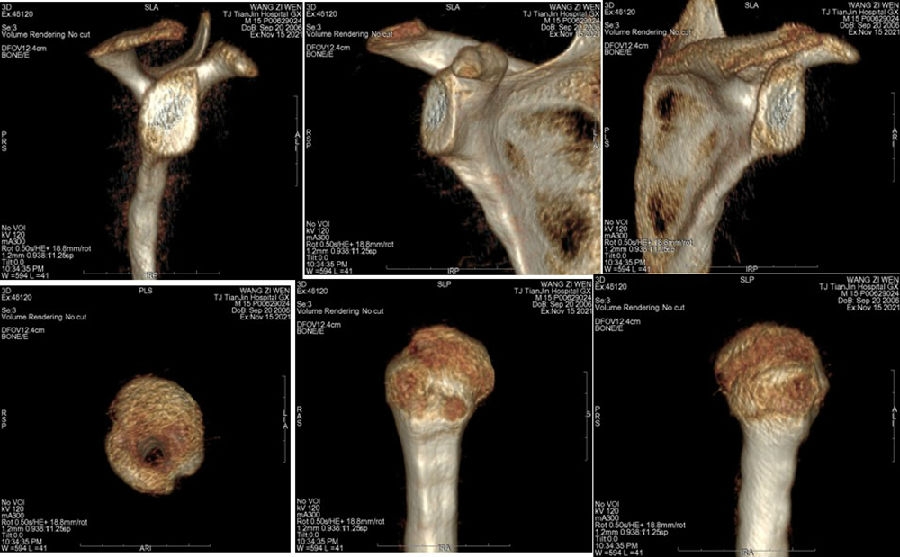

典型病例,王XX,男性,15岁。主诉右肩外伤疼痛、活动受限1月。既往半年前有肩关节脱位病史。

图37 既往肩关节脱位时,急诊所拍的X线片

图38 复位后的肩关节CT

图39 此次复发脱位MR评估

图40 影像学评估

双侧CT三维扫描显示:D=34mm,d=3mm,d/D=肩胛盂骨缺损9%;GT=25.2mm,HIS=30mm。

该患者为轨迹外Hill-Sachs损伤,需要做bankart修补,同时轨迹外做remplissage手术。